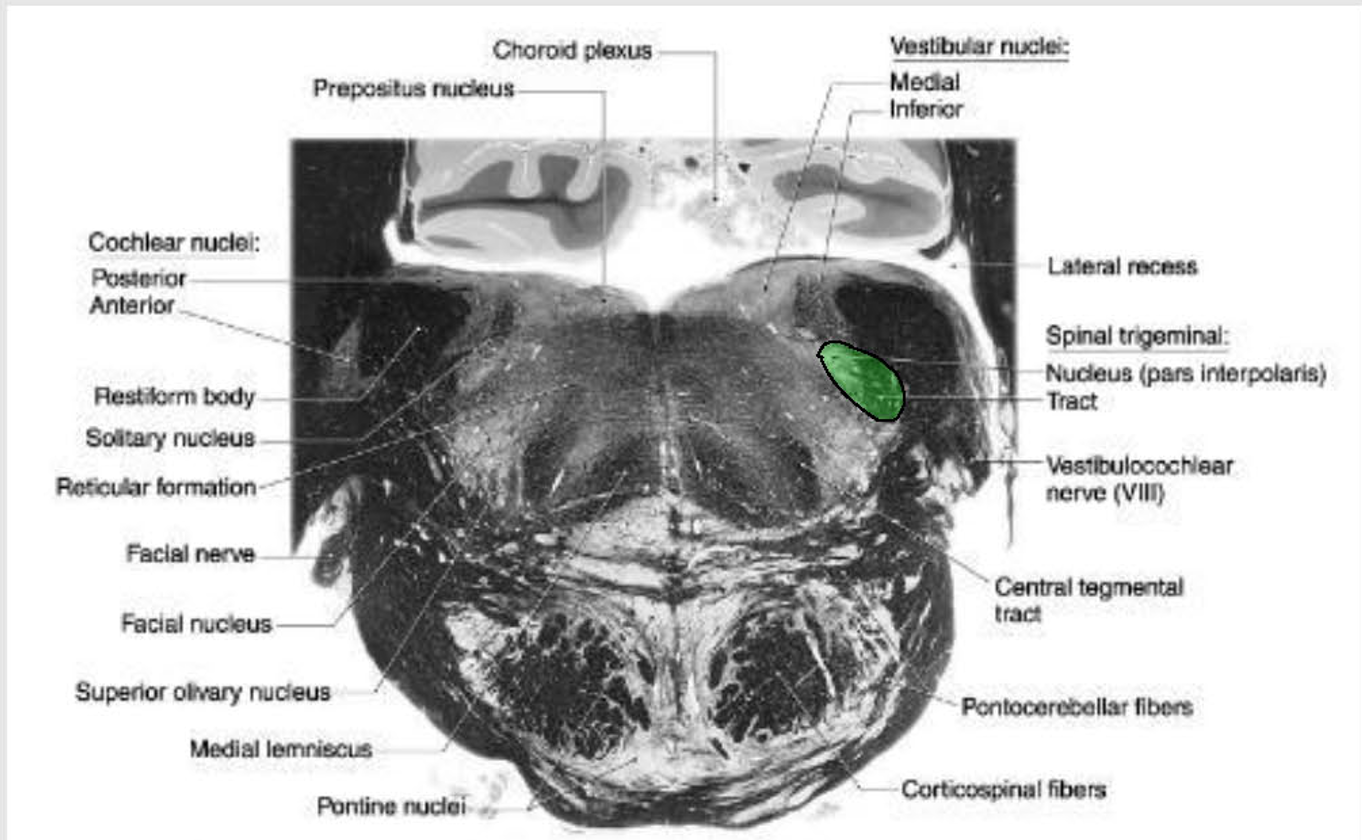

location of major tracts in the Caudal Pons:

CST/corticonuclear (bulbar) run through the substance of the basilar pons

Medial Lemniscus:

still in the midline

begins to turn → somatotopy shifts → leg areas = more lateral

anterolateral system

still in lateral position w/in pontine tegmentum,

@ anterolateral edge w/ formation of middle cerebellar peduncle.

Rubrospinal Tract:

Dorsal to ALS

Reticulospinals and vestibulospinals

still being formed in this area, so they are not clear.

spinal nucleus and tract of CN V

still present as pars oralis

just dorsal to the exit of the facial nerve.

MLF and tectospinal (tectobulbospinal ) tracts

dorsal position near the midline.

will now carry motor information for eye movements.

Other Ascending/Descending → displaced into the pontine tegmentum